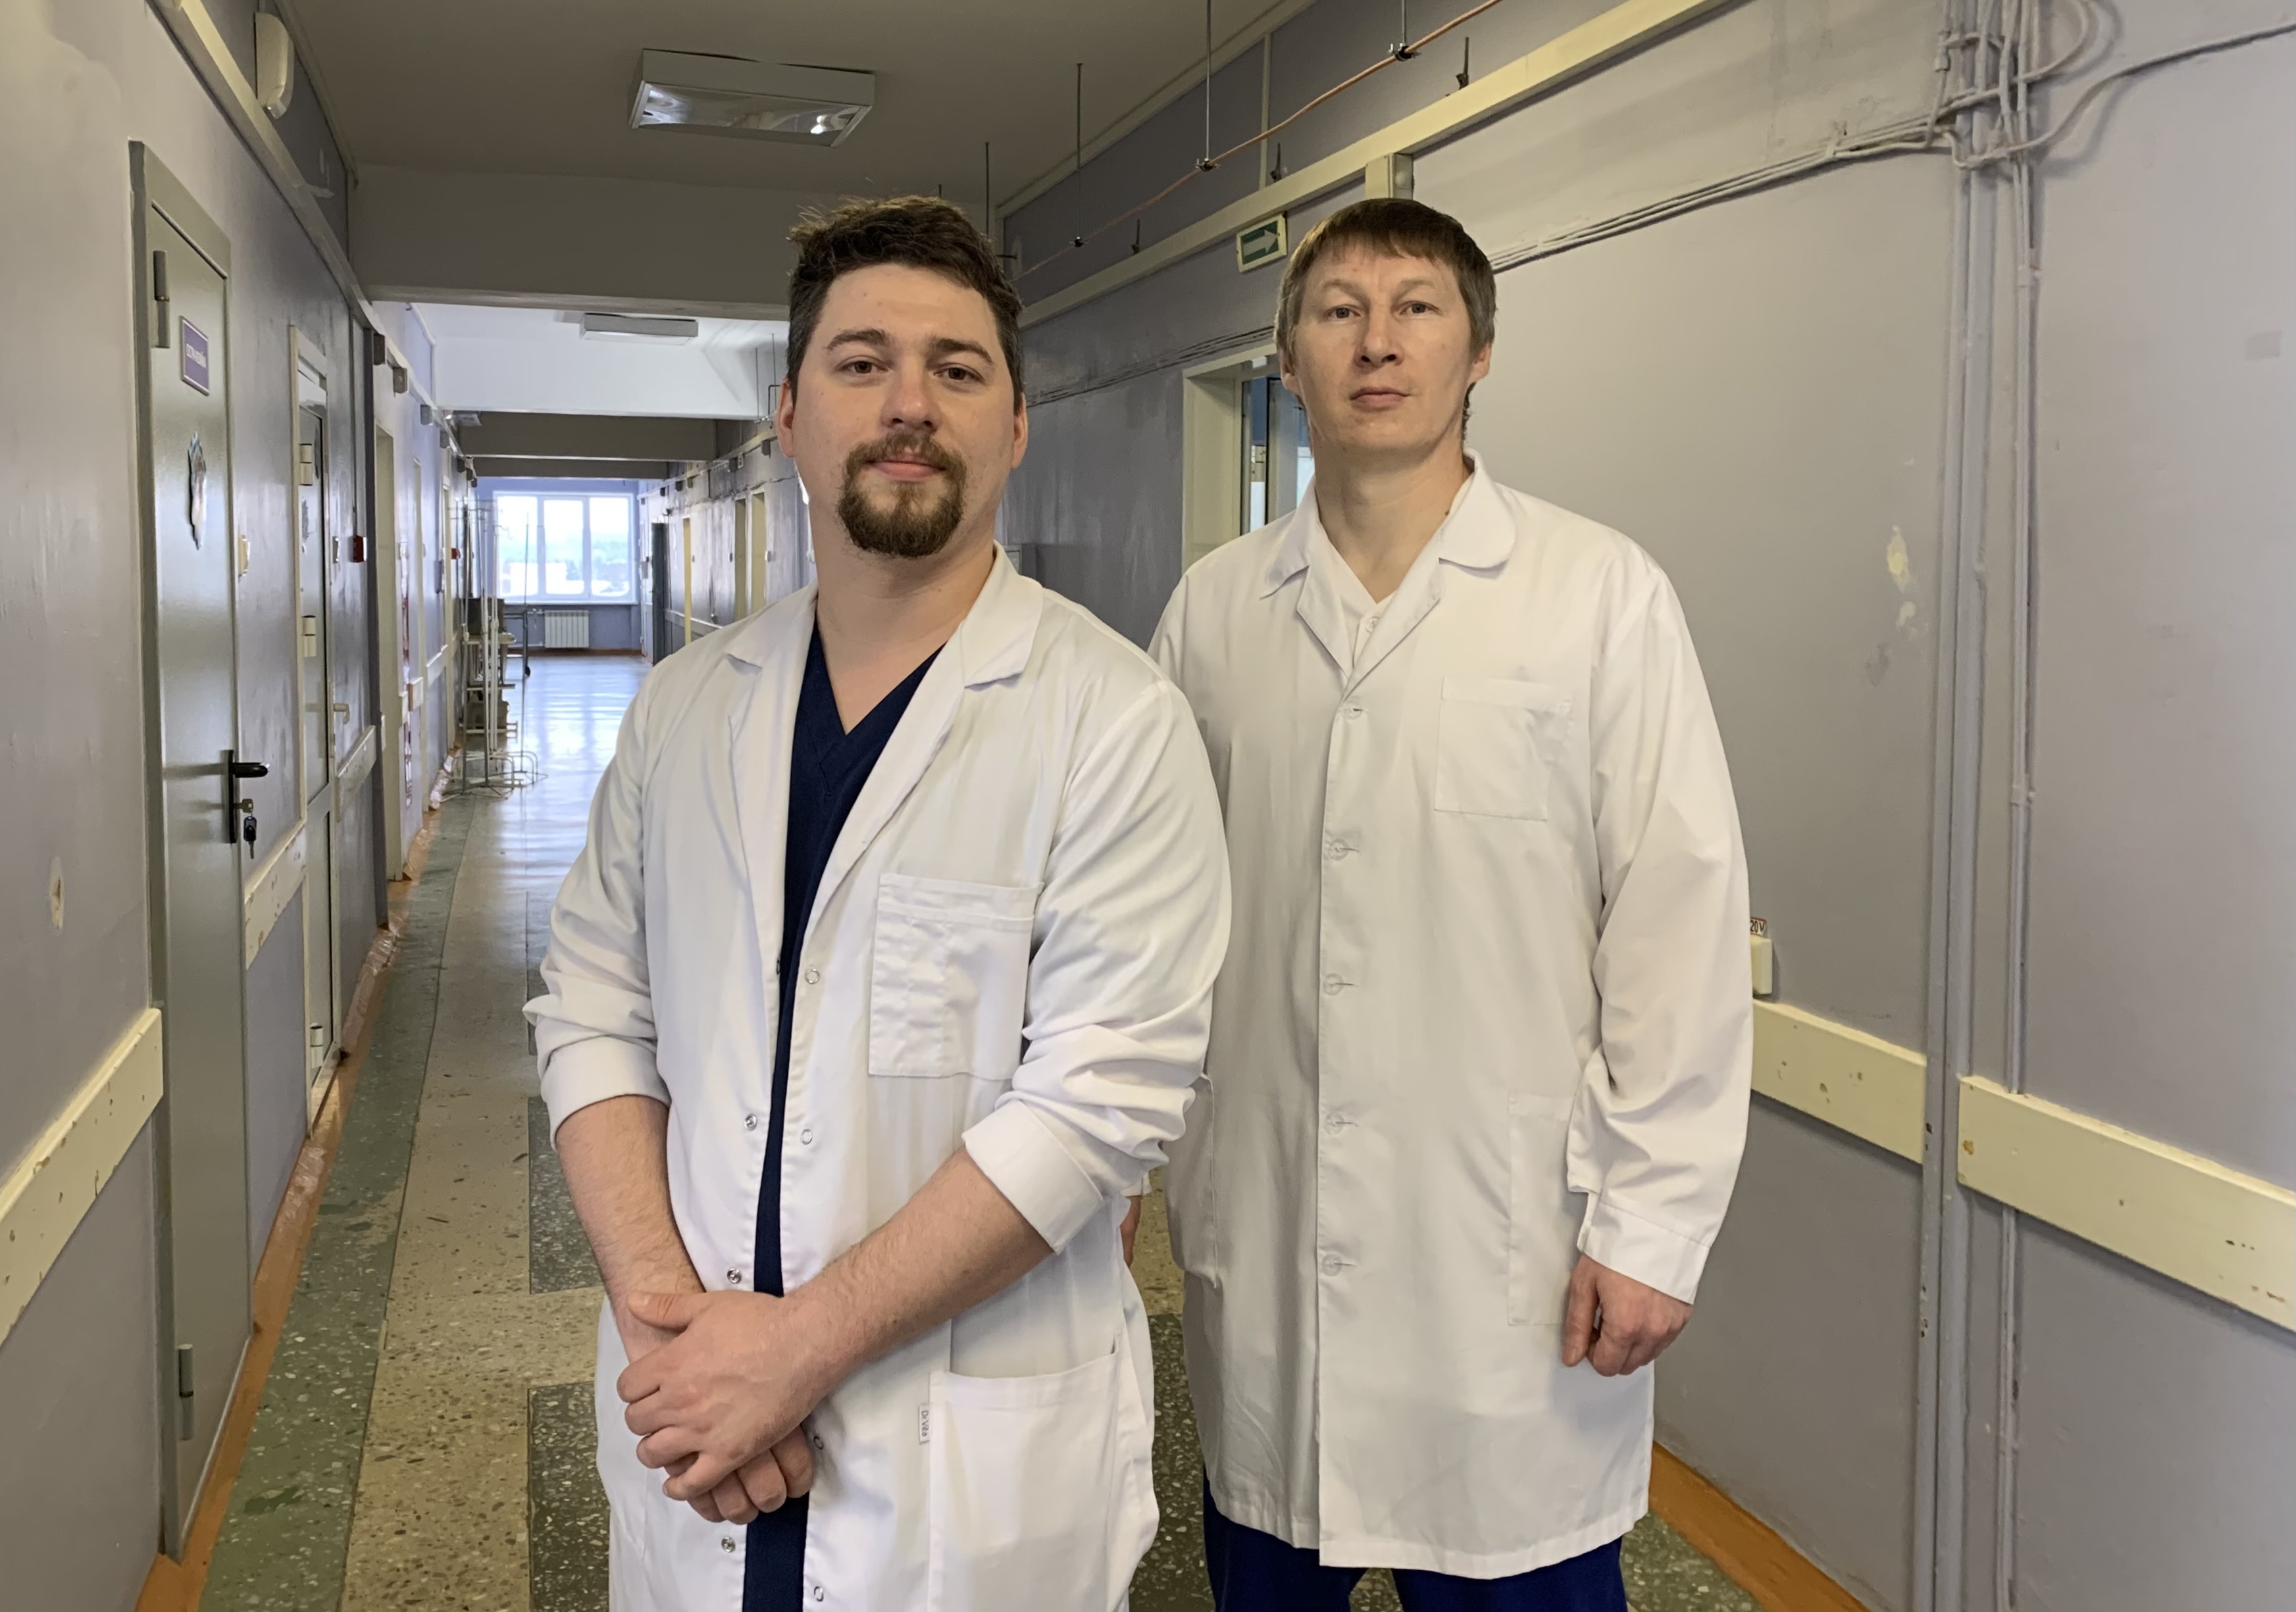

Врачи приняли решение провести экстренную операцию. За 3,5 часа нейрохирурги Дмитрий Неволин и Кирилл Погребняк открытым методом смогли полностью удалить новообразование. Провести микрохирургическую операцию с высокой точностью и эффективностью помог специальный нейромикроскоп, который был получен медучреждением в 2021 году по программе модернизации первичного звена здравоохранения. По результатам гистологического исследования специалисты определят дальнейшую тактику лечения пациентки.

«На счету наших нейрохирургов не один десяток сложнейших операций по передовым методикам лечения травм и заболеваний. Современное оборудование и традиции школы нейрохирургов Городской больницы №1 позволяют оказывать качественную нейрохирургическую помощь тагильчанам на местном уровне, без поездок в областной центр», — отметил главный врач ГБ №1 Александр Павловских.